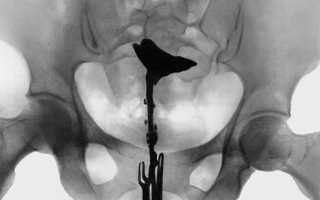

Гистеросальпингография маточных труб (метросальпингография) представляет собой рентгенологическое исследование особенностей полости матки и проходимости маточных труб. Это информативный способ изучения строения и функции репродуктивной системы женщины. Кроме этого метода существуют:

Процедура гистеросальпингографии проводится в специальном кабинете, оборудованном рентген-аппаратом.

1. Женщина ложится на гинекологическое кресло. Во влагалище вводятся гинекологические зеркала для получения доступа к шейке матки.

2. Влагалище и шейка матки обрабатываются антисептиком. В цервикальный канал устанавливается канюля.

3. Зеркала извлекаются, и женщина ложится горизонтально.

4. По специальной трубке небольшими порциями в полость матки вводится стерильное контрастное вещество, содержащее йод (урографин, венографин, уротраст и др.).

5. По мере заполнения им матки и маточных труб производится серия рентгенологических снимков. Длительность исследования зависит от индивидуальных особенностей женщины.

Результаты гистеросальпингографии позволяют лечащему врачу сделать вывод об особенностях строения полости матки и маточных труб.

• Исследование может показать частичную или полную непроходимость маточных труб. В случае полной непроходимости контрастное вещество не выявляется в брюшной полости.

• Колбообразное расширение маточной трубы может иметь место при гидросальпинксе.

• Неровность контура полости матки и дефект ее наполнения свидетельствует о наличии полипа эндометрия или субмукозной миомы матки.